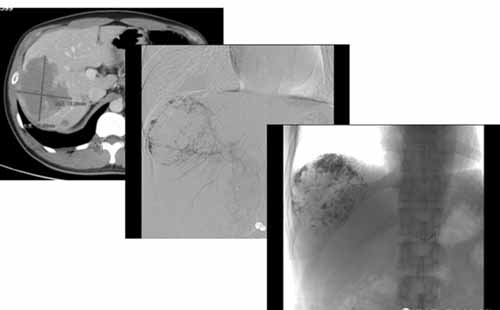

肝血管瘤的介入栓塞硬化治療,即經(jīng)導(dǎo)管肝動脈栓塞術(shù)( TAE) ,手術(shù)方法為:介入醫(yī)師采用Selding er 技術(shù), 經(jīng)股動脈穿刺,用導(dǎo)管或微導(dǎo)管在導(dǎo)絲指引下, 選擇或超選擇造影, 明確肝血管瘤的大小、部位、多少。然后將導(dǎo)管頭端插入血管瘤的供血動脈( 靶血管) , 選擇合適的栓塞材料,在監(jiān)視下緩慢栓塞。根據(jù)患者的狀況, 血管瘤栓塞滿意后, 再用明膠海綿條將血管瘤的供血動脈閉塞。栓塞完畢行肝動脈造影以評定栓塞效果。巨大型的血管瘤可分期、分次栓塞。

我們來看一個典型病例:

(手術(shù)過程:通過DSA下動脈造影,找到供血動脈,注入栓塞劑進行栓塞。)